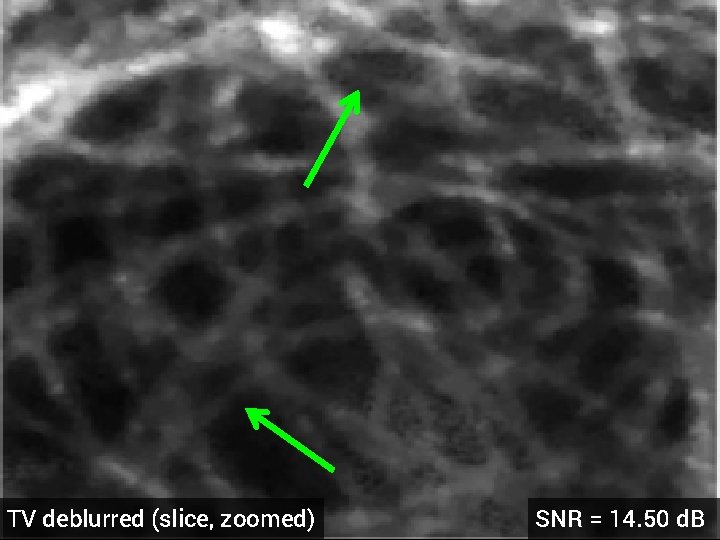

Deblurring of 3 -D Florescence Microscopy § 1024 x 17 voxels § 3 x 3 x 3 Gaussian blur kernel, std. dev = 0. 05 § 5 d. B additive Gaussian noise § Optimized regularization parameter original dataset (z-slice)

Blurred + Noisy (slice, zoomed)

TV deblurred (slice, zoomed) SNR = 14. 50 d. B

HDTV 3 deblurred (slice, zoomed) SNR = 15. 23 d. B